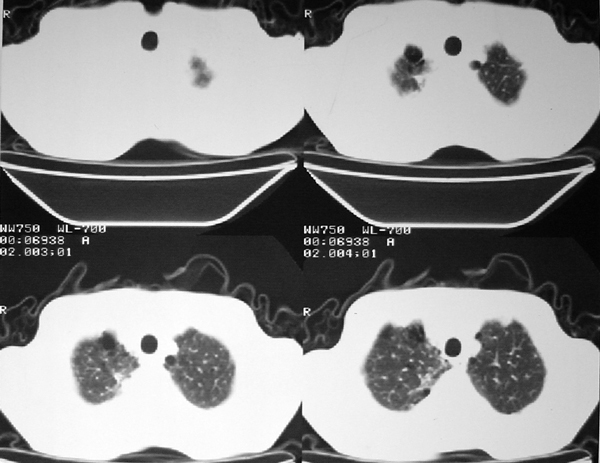

右肺囊实性占位 患者拒绝穿刺活检  近期始终间断性发高烧 使用消炎控制, 左鼻翼部有多发皮肤溃疡

双肺呈毛玻璃状,胸膜旁有多个小囊状气腔。右下囊实性病灶内有园形气体影,边缘光滑,与之相连的胸膜稍增厚,间断发热,抗炎效果不好。考虑机会性感染可能性大。

右下肺占位性病变,其边缘较光整无明显分叶,似有包膜,邻近胸膜无凹陷征及牵拉征象,包块内见数个大小不等气液面及不规则透亮影,纵隔未见明显淋巴结肿大。结合上次ct检查,考虑:炎性包块或真菌感染包块可能性大,周围型肺癌可能性小。